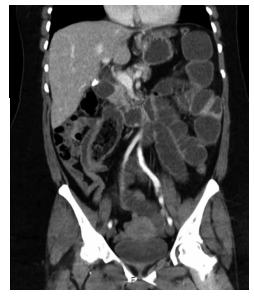

Mulher de 41 anos apresentou quadro de diverticulite aguda perfurada e bloqueada, sendo submetida à laparoscopia com limpeza e drenagem da cavidade. Evoluiu bem no

pós-operatório, com dreno progressivamente menos produtivo e retirado no 10º PO. Retorna 2 meses após a cirurgia, assintomática, afebril, sem dor abdominal, mas com

secreção purulenta diária por orifício cutâneo no local do

dreno, em pequena quantidade, suficiente para sujar uma

gaze por dia. Foi realizada uma tomografia de abdome,

demonstrada nas imagens a seguir:

Sobre a evolução deste quadro, assinale a alternativa correta.